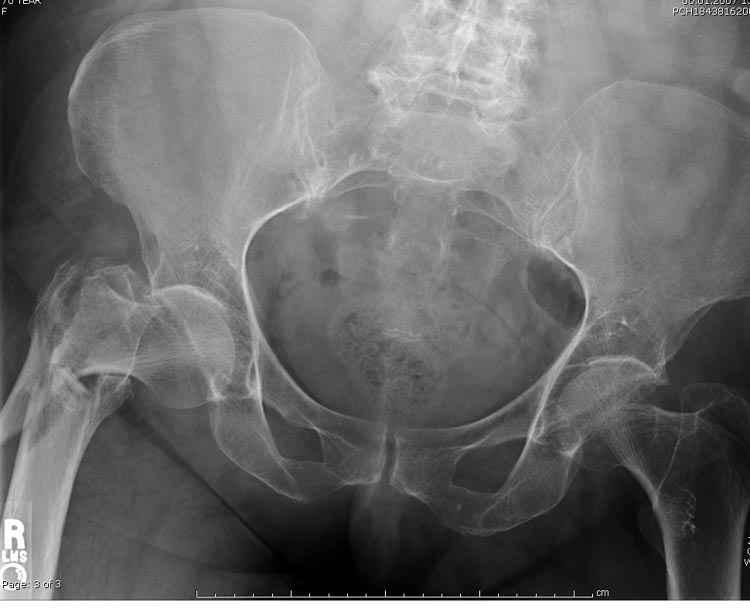

Re: оскольчатый чрезвертельный перелом

А что тут заставляет сомневаться? Здесь настолько очевидно предпочтителен закрытый интрамедуллярный остеосинтез реконструкционным стержнем (проксимальные гвозди толстоваты для такого молодого возраста), что закрадывается мысь о каком-то подвохе.

Уже ставшие традиционными вопроосы - что доступно на месте и каковы собственные намерения?

Желательно бы и снимок бедра на протяжении и в другой проекции.

Не солидно экономить на пленке, это не делает чести презентации. Такие ограниченные нестандартные снимки приводят к тактическим ошибкам.

Предугадать распространение линий перелома при чрезвертельных и оскольчатых переломах трудно, поэтому для принятия правильного решения рекомендуется Компьютерно Томографические исследование.

При отсутствии КТ, снимок на вытяжении поможет увидеть общую картину расположения отломков, особенно потенциальные места введения импланта. Риск раскола в этом случае огромный, поэтому больной должен быть дообследован.

А так для лечения оскольчатых переломов подходят все методы, включая интра- и экстрамедуллярные в зависимости от опыта и наличия импланта.